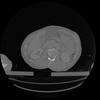

34 CUERPO,CE,Vol,1.0,CUERPO,,